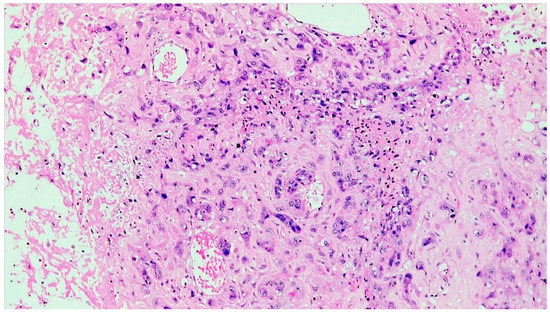

2. Case Presentation